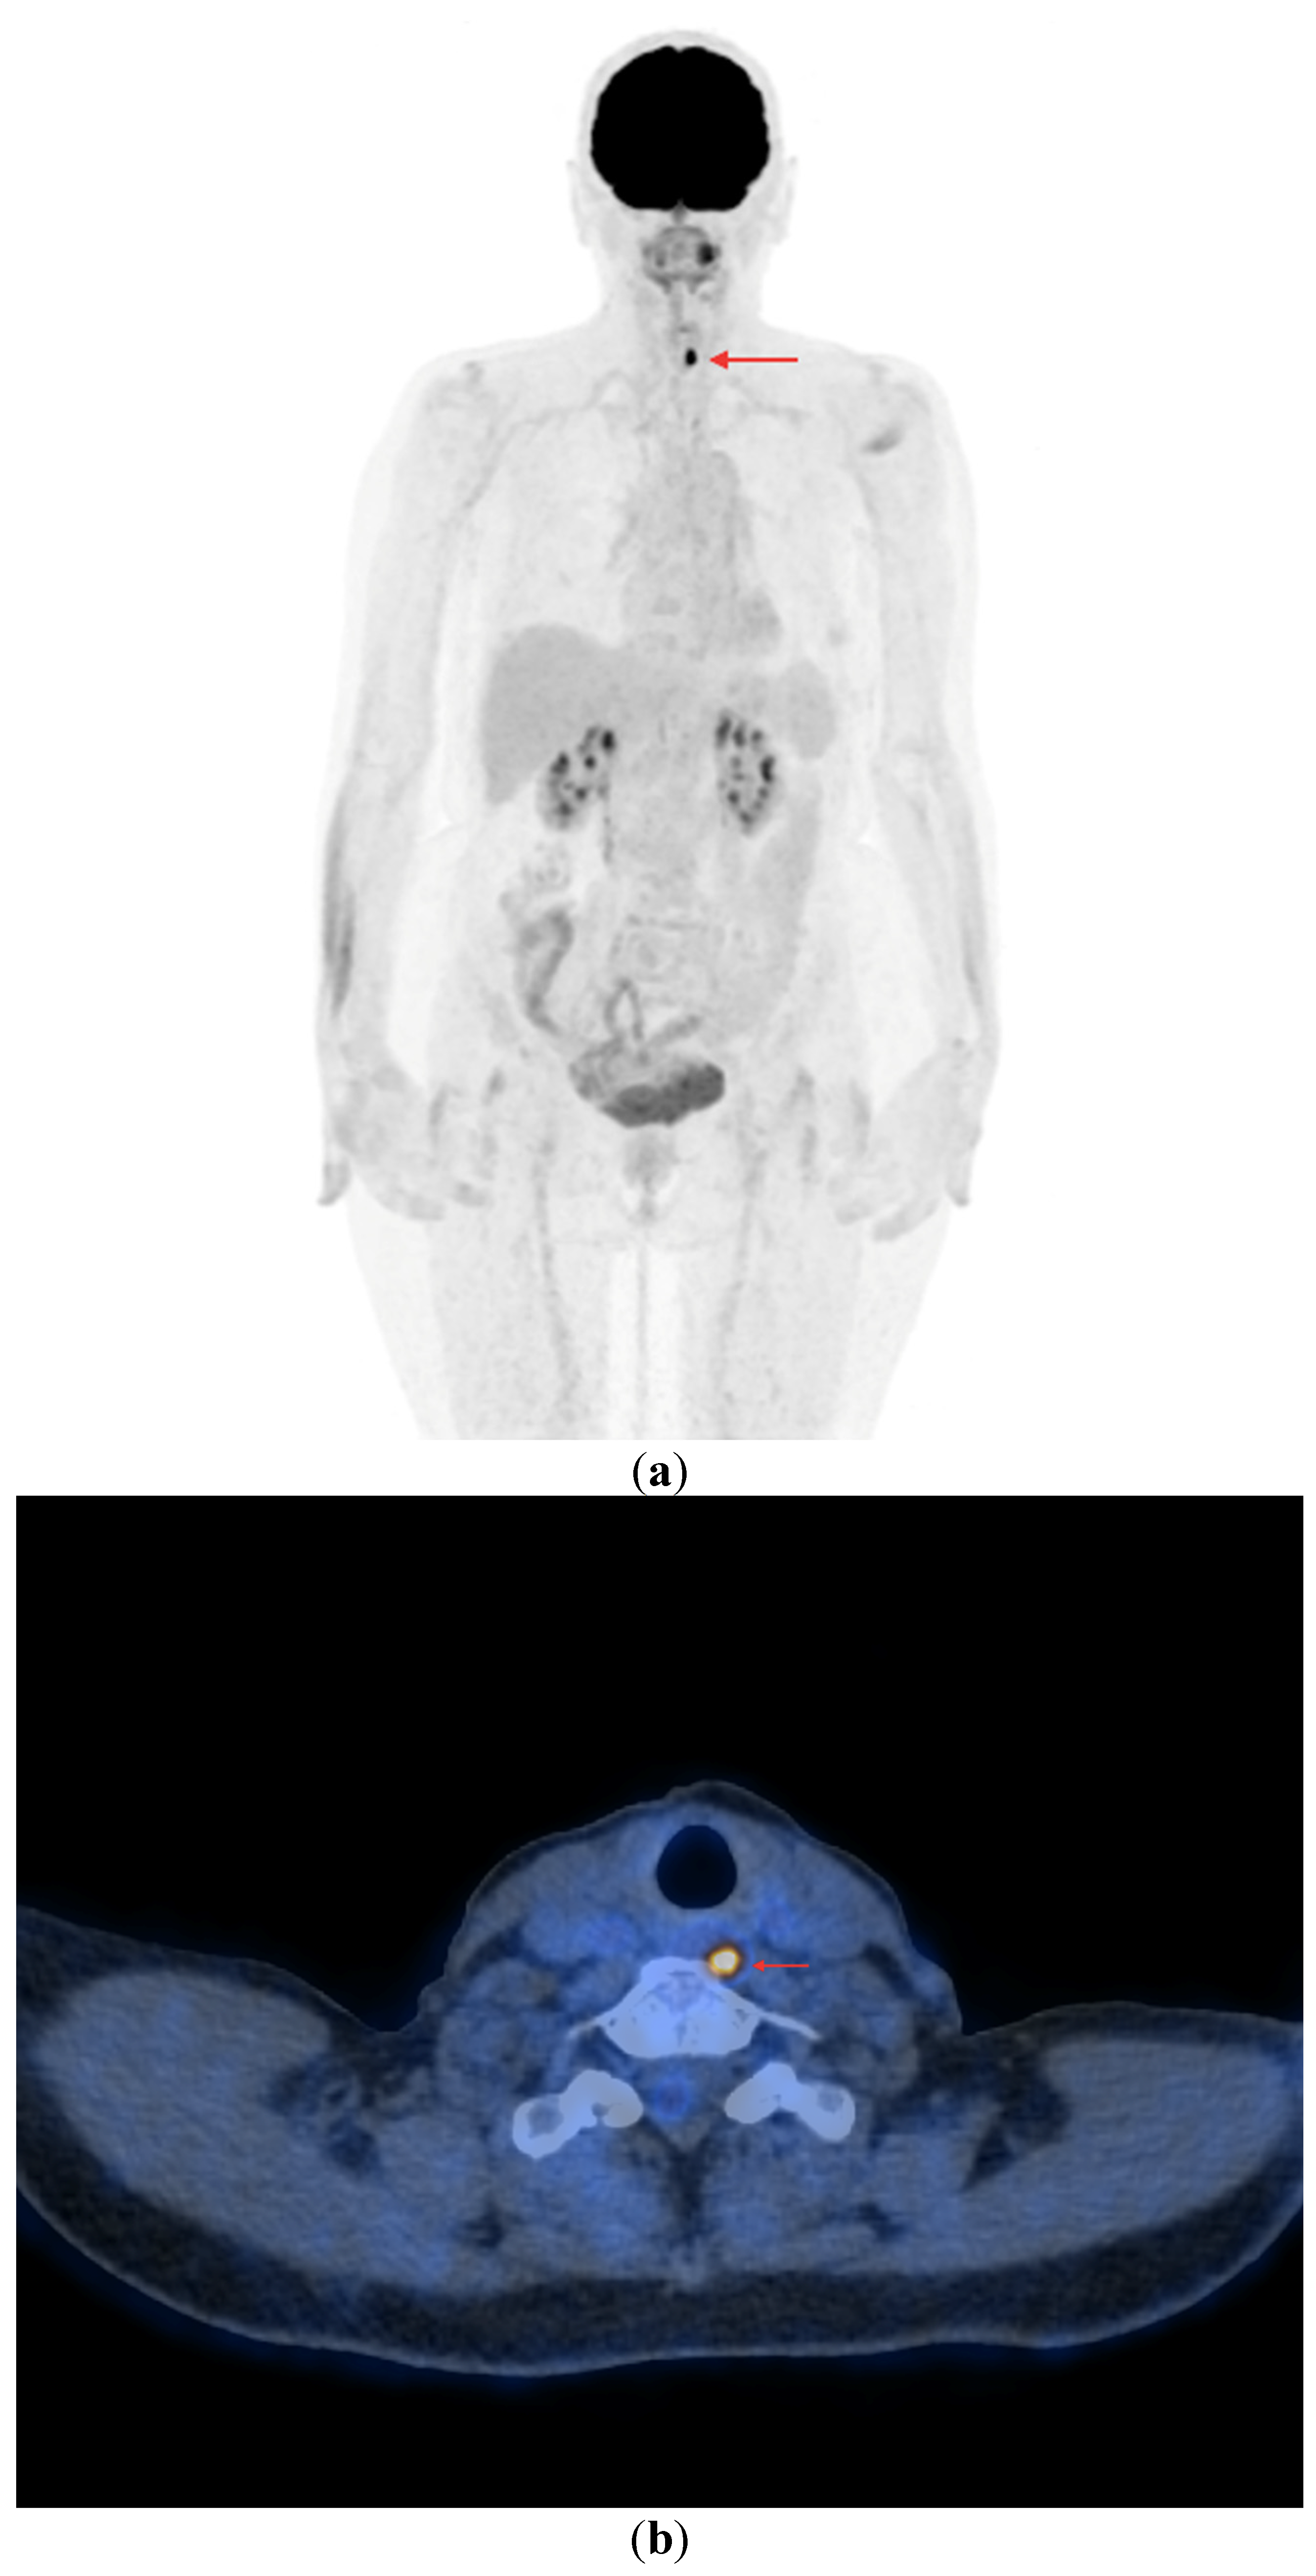

Figure 5.

Maximum-intensity projection (MIP) PET/CT with [18F]FDG. Multiple foci of increased [18F]FDG accumulation are visible in the neck (unresectable local recurrence), with the presence of metastatic lesions in the lymph nodes and in both lungs. Patient qualified for TKI (sorafenib) therapy with stable disease since 2022.